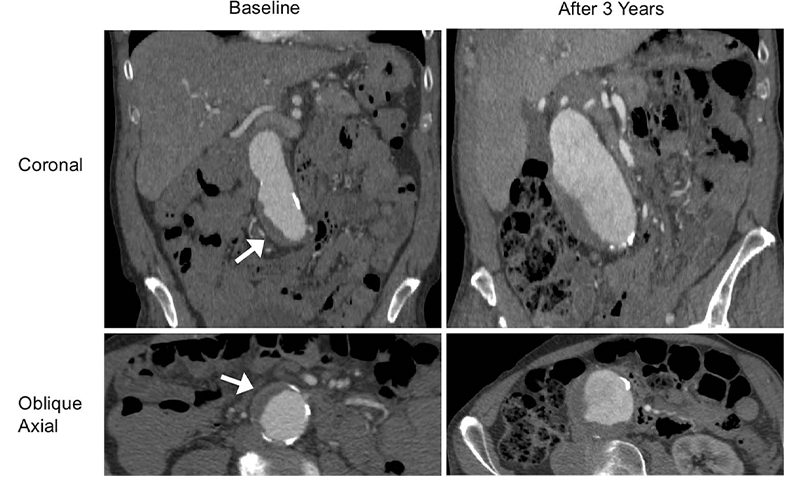

Dr. Zhu and colleagues focused their study on the intraluminal thrombus, a blood clot on the wall of the aorta at the location of the aneurysm. Intraluminal thrombi are present in the majority of aneurysms close to the repair threshold of 5.5 cm, and in a considerable number of smaller aneurysms. Despite their prevalence, the influence of these clots on abdominal aortic aneurysm growth and rupture risk is still not fully understood.

Slightly more than half of patients had an intraluminal thrombus. The aneurysms of those with intraluminal thrombus were larger at baseline and grew by a rate of 2 millimeters (mm) per year, twice as fast as the 1 mm per year growth rate in people without intraluminal thrombus.

“An aneurysm with thrombus grows much faster than one without a thrombus,” Dr. Zhu said. “Our study looked at a large number of patients with a relatively long follow-up to confirm that thrombus is a new risk factor that may be potentially reported by radiologists.”